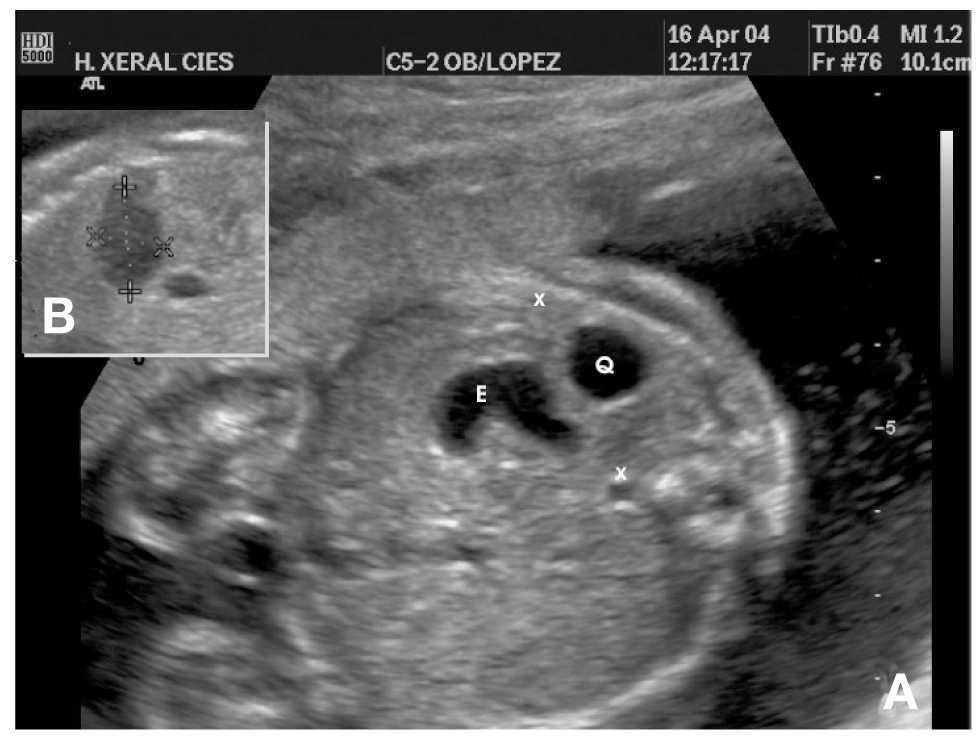

Figura 1.A: visión transversal del abdomen fetal. Se observa el estómago fetal (E), el quiste esplénico (Q) y los límites del bazo señalados con una X. B: detalle del quiste esplénico en una proyección longitudinal.

Gestante de 28 años, sin antecedentes personales de interés. En el estudio ecográfico de la semana 20 de gestación se detecta una imagen quística de 1 cm de diámetro en el cuadrante superior izquierdo del abdomen fetal, que se interpreta en un primer momento como sospecha de doble cámara gástrica. Con este diagnóstico se remite para un nuevo examen ecográfico de alta resolución en la unidad de diagnóstico prenatal. El estudio ecográfico realizado en esta unidad mediante un sistema de ultrasonidos HDI 5000 (Sistemas Médicos Philips) detecta un quiste esplénico de 17 * 10 * 11 mm de paredes lisas, sin ecos en su interior y que protruye ligeramente en la cámara gástrica (fig. 1). La suprarrenal izquierda es normal, pero con un ligero desplazamiento por el crecimiento esplénico. Se asocia a una ligera esplenomegalia con un desplazamiento del bazo fetal hacia la línea media, lo que produce una ligera compresión vascular de la vena cava inferior. La eco-Doppler de la arteria esplénica, umbilical, cerebral, cardíaco y venoso, es normal para la edad gestacional. El resto de la exploración fetal es normal, con una biometría acorde a la edad gestacional. En un estudio ecográfico previo, en la semana 14, no se observó ninguna masa quística abdominal y era acorde a la edad gestacional. Con el diagnóstico de quiste esplénico de probable etiología linfangiomatosa, se inicia el protocolo diagnóstico, realizándose cariotipo fetal (46XY) y serologías para toxoplasma, citomegalovirus y parvovirus B19, todas negativas. La imagen 4D muestra el quiste en la región superior esplénica (fig. 2). Para el examen 4D se utilizó un sistema de ultrasonidos Voluson 730 Expert (General Electric). Los controles ecográficos seriados del quiste demuestran una tendencia a la disminución, llegando a unos escasos 3 mm en la semana 35 (fig. 3). El crecimiento fetal fue acorde a la edad gestacional y los estudios Doppler en la arteria umbilical y en la arteria cerebral media fueron normales durante toda la gestación.

En el estudio mediante ecografía 2D pudimos detallar el diagnóstico y delimitar las relaciones de la masa con estructuras vecinas (fig. 1). El estudio mediante 4D permitió obtener unas imágenes muy demostrativas de la relación y la situación del quiste con el propio bazo, reconstruyendo una imagen esplénica en la que fácilmente se observaba la exacta localización del quiste (fig. 2).